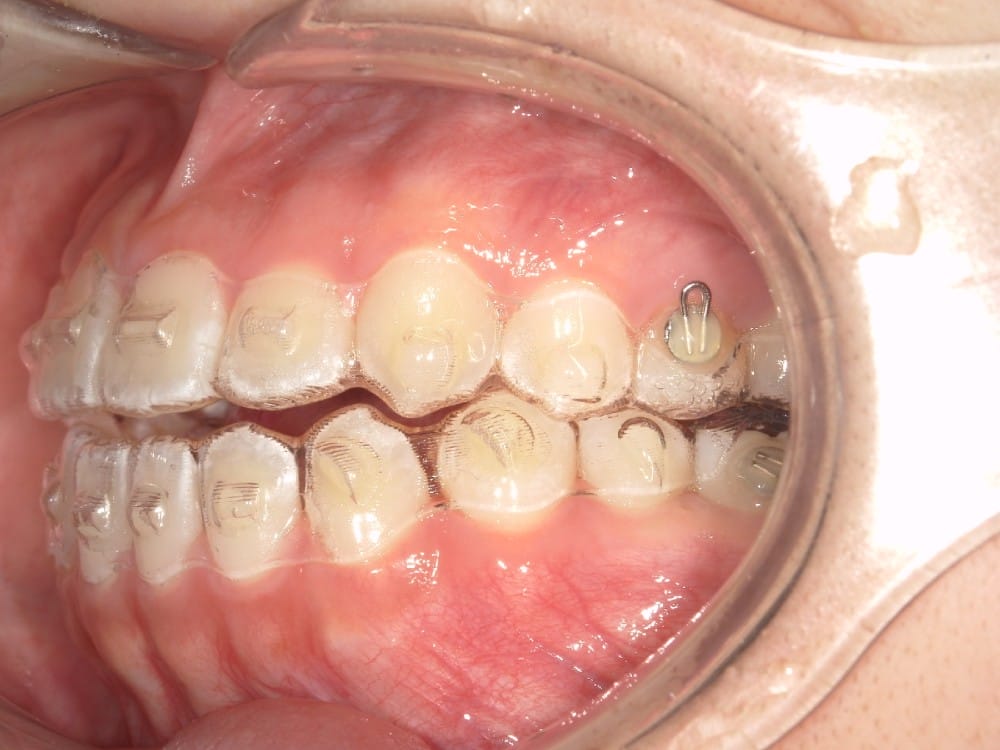

最後の画像のように奥歯のズレが1本以上あるケースでは、歯列矯正のみでの受け口の改善は困難と判断することが多いです。

このような奥歯の移動量が大きい症例では、マウスピースだけでは難しいことがあり、カリエールとよばれる装置を補助的に使用し、上下の噛み合わせの前後関係を整えることで、手術を行わずに機能面と見た目の両方が改善することがあります。

一時的に前歯は噛み合わせが開いていますが、受け口の矯正では、最終段階で前歯ばっかりあたって奥歯がしっかり噛まないということも起こりやすいので、あえて狙って動かしています。

ここから上下透明なマウスピースに変え、仕上げていきました。

今回のケースも奥歯の移動量が大きいため、マウスピースだけでは難しいと判断し、カリエールとよばれる装置を補助的に使用し、上下の噛み合わせの前後関係を整えることで、手術を行わずに機能面と見た目の両方が改善することにしました。

治療中の直近の写真です。生まれつき小さな歯である前から両側の2番目の歯は、被せ物をして見た目の回復をする予定にしています。